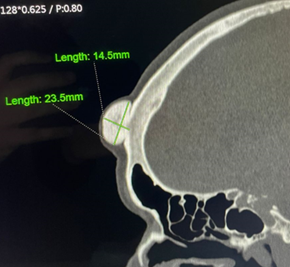

An 85 years old female patient from Guarenas, Miranda state, with a history of arterial hypertension, who reports the onset of the current disease 20 years prior to the first medical consult, characterized by a progressive frontal tumor growth that was self-detected, with an important aesthetical awkwardness and progressive headache, which is why she goes to the Plastic and Reconstructive Unit of the Caracas University Hospital (Figure 1). With a personal history of a controlled hypertensive cardiopaty, on physical examination, the patient was in well general condition, neck and head at the frontal region she had an impressive increase in volume is evidence emerging from the external cortical of the frontal bone with irregular edges, of firm, non-mobile consistency, adhered to deep planes, approximately 2.4 x 1.5 cm. For this reason, a simple tomographic study was performed progressing from the base to the vertex, with multiplanar reconstruction and bone window: At the level of the external cortex of the right frontal bone, a hyperdense exophytic image in the calcium range, with defined edges, with a hypodense center with a trabeculated appearance, measures 2.3 x 1.45 x 2.1 cm. There were no lytic lesions or fracture lines in the cranial vault without soft tissue involvement (Figure 2 & 3). For this reason, with the respective preoperative aconditionation and appropriate blood pressure levels, the patient was taken to the operation room and performed following rules of asepsis and antisepsis, under sedation, supine position, placement of surgical fields, a transverse incision is made in the line of implantation of the scalp, division through planes and soft tissues until reaching a Bone lesion at the expense of the external table of the left frontal region of approximately 4 x 3 cm of firm consistency, edges are released, use of osteotome and disinsertion of the osteoma of the frontal bone, use of electro scalpel and application of bone wax, verification of hemostasis, closure by planes with vicryl 4-0 and prolene 4-0. Final cure. The histological results of the biopsy reports an osteoid osteoma completely resected (Figure 4).

Figure 4 At the external cortical level of the right frontal bone, hyperdense exophytic image in the calcium range, with defined edges, with a hypodense center with a trabeculated appearance compatible with probable osteoid osteoma.